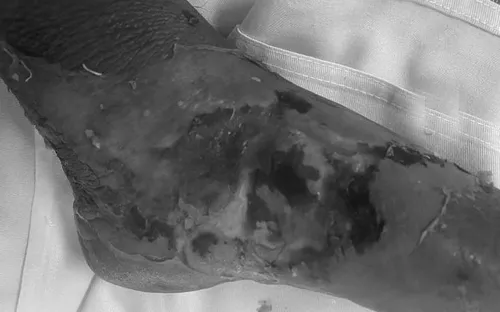

Cảnh báo nhiễm trùng nặng do tự ý đắp lá cây lên vết thương

VTV.vn - Chỉ từ vết gai đâm nhỏ, người bệnh 80 tuổi bị nhiễm trùng phần mềm nặng do tự ý đắp lá cây, phải điều trị tích cực tại cơ sở y tế.